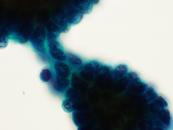

第38回日本臨床細胞学会九州連合会学会(熊本)スライドカンファレンス症例3

種別:消化器・口腔

出題:甲斐 敬太 佐賀大学医学部附属病院病理部

| 年齢 | 60代 | 性別 | 男性 |

|---|---|---|---|

| 採取部位 | 胆汁 | 採取方法 | 経皮経肝胆道ドレナージ |

| 検体処理法 |

臨床所見

既往歴:潰瘍性大腸炎治療中。

現病歴:難治性の十二指腸潰瘍を合併し、通過障害をきたしていた。閉塞性黄疸が出現し、精査で原発性硬化性

胆管炎が疑われた。減黄目的に経皮経肝胆道ドレナージが行われ、胆汁が提出された。なお、狭窄部の

胆管と十二指腸潰瘍部から生検が行われたが、悪性所見は指摘できなかった。

| 正解 | 5.腺癌 |

▼選択肢及び投票結果

| 1.急性胆管炎 (反応性異型) | 1件 | (1.0%) | |

| 2.原発性硬化性胆管炎 (反応性異型) | 25件 | (24.0%) | |

| 3.Low-grade BilIN | 31件 | (29.8%) | |

| 4.Low-grade IPNB | 19件 | (18.3%) | |

| 5.腺癌 | 28件 | (26.9%) | |

| 投票総数 | 104件 | (100%) |